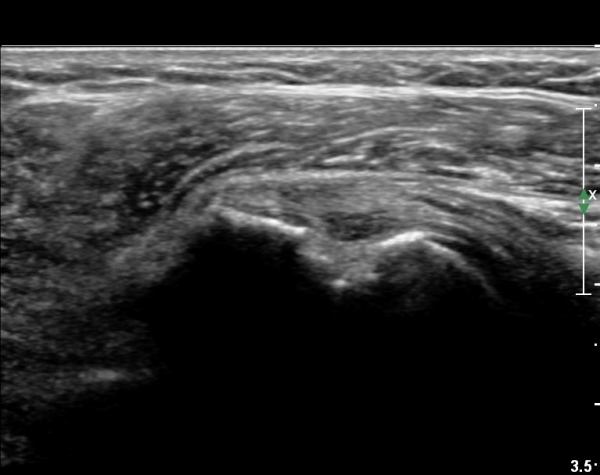

ȸÀü±Ù°³°£°Ý(rotator cuff interval) Ⱦ´Ü¸é°Ë»ç¿¡¼­ ÀÌµÎ¹Ú±Ù°Ç ¿ÜÃø¿¡ ±Ø»ó°ÇÀÌ °üÂûµÇÁö ¾Ê°í

´ë°áÀý Ç¥ÃþÀÇ »À°¡ ¿ïÅüºÒÅüÇÏ°Ô º¯ÇÏ¿´´Ù(±×¸² 1, 2)

ÀÌ´Â ½ÉÇÑ Ãæµ¹ÁõÈıºÀÇ °á°úÀ̰í ȸÀü±Ù°³ ÆÄ¿­À» °­·ÂÈ÷ ¾Ï½ÃÇÏ´Â ¼Ò°ßÀÌ´Ù.